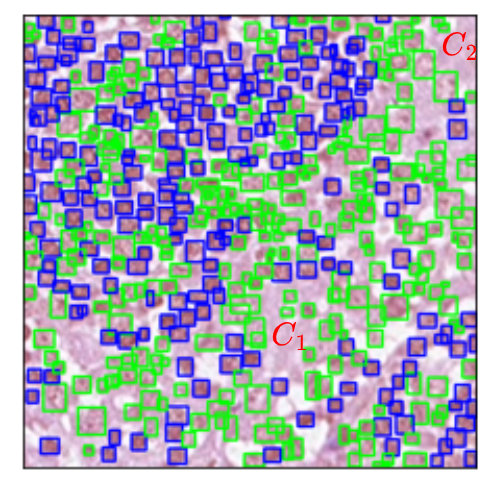

Refer to captionRefer to captionRefer to captionRefer to captionRefer to captionRefer to captionRefer to captionRefer to captionRefer to captionRefer to captionRefer to captionRefer to captionOriginalGround TruthBaselineProposed

Figure 3: Qualitative performance of DeGPR. The third and fourth columns show Yolov5, with and without DeGPR. The first row is an image from MuCeD, with red and blue bounding boxes corresponding to IELs and ENs. The bounding boxes A1,A2,A3subscript𝐴1subscript𝐴2subscript𝐴3A_{1},A_{2},A_{3} show improvement in detecting missing cells and A4subscript𝐴4A_{4} shows improvements in misclassification. Row two is from the CoNSeP dataset with Inflammatory (red), Epithelial (blue), and Spindle (green) cells. Bounding boxes C1subscript𝐶1C_{1} and C2subscript𝐶2C_{2} show improvements in misclassification. Finally, the fourth row from the MoNuSAC dataset shows Epithelial (red), lymphocyte (blue), Neutrophil (green), and Macrophage (cyan) cells. D1subscript𝐷1D_{1} shows improvement in bounding box prediction, while D2subscript𝐷2D_{2} shows improvement in misclassification.

Qualitatively, we illustrate model predictions in Fig 3. The first column depicts the original image, the second is ground truth bounding boxes, the third shows the image with predictions from the Yolov5 baseline model, while the final column shows predictions from the Yolov5 with DeGPR. Three rows contain an exemplar image each from MuCeD, CoNSeP, and MoNuSAC, respectively. We note that DeGPR reduces both misclassification and misidentification errors. The highlighted bounding boxes A1,A2,A3subscript𝐴1subscript𝐴2subscript𝐴3A_{1},A_{2},A_{3} show improvement in the detecting missing cells, and A4,C1,C2,D2subscript𝐴4subscript𝐶1subscript𝐶2subscript𝐷2A_{4},C_{1},C_{2},D_{2} show reductions in misclassification.